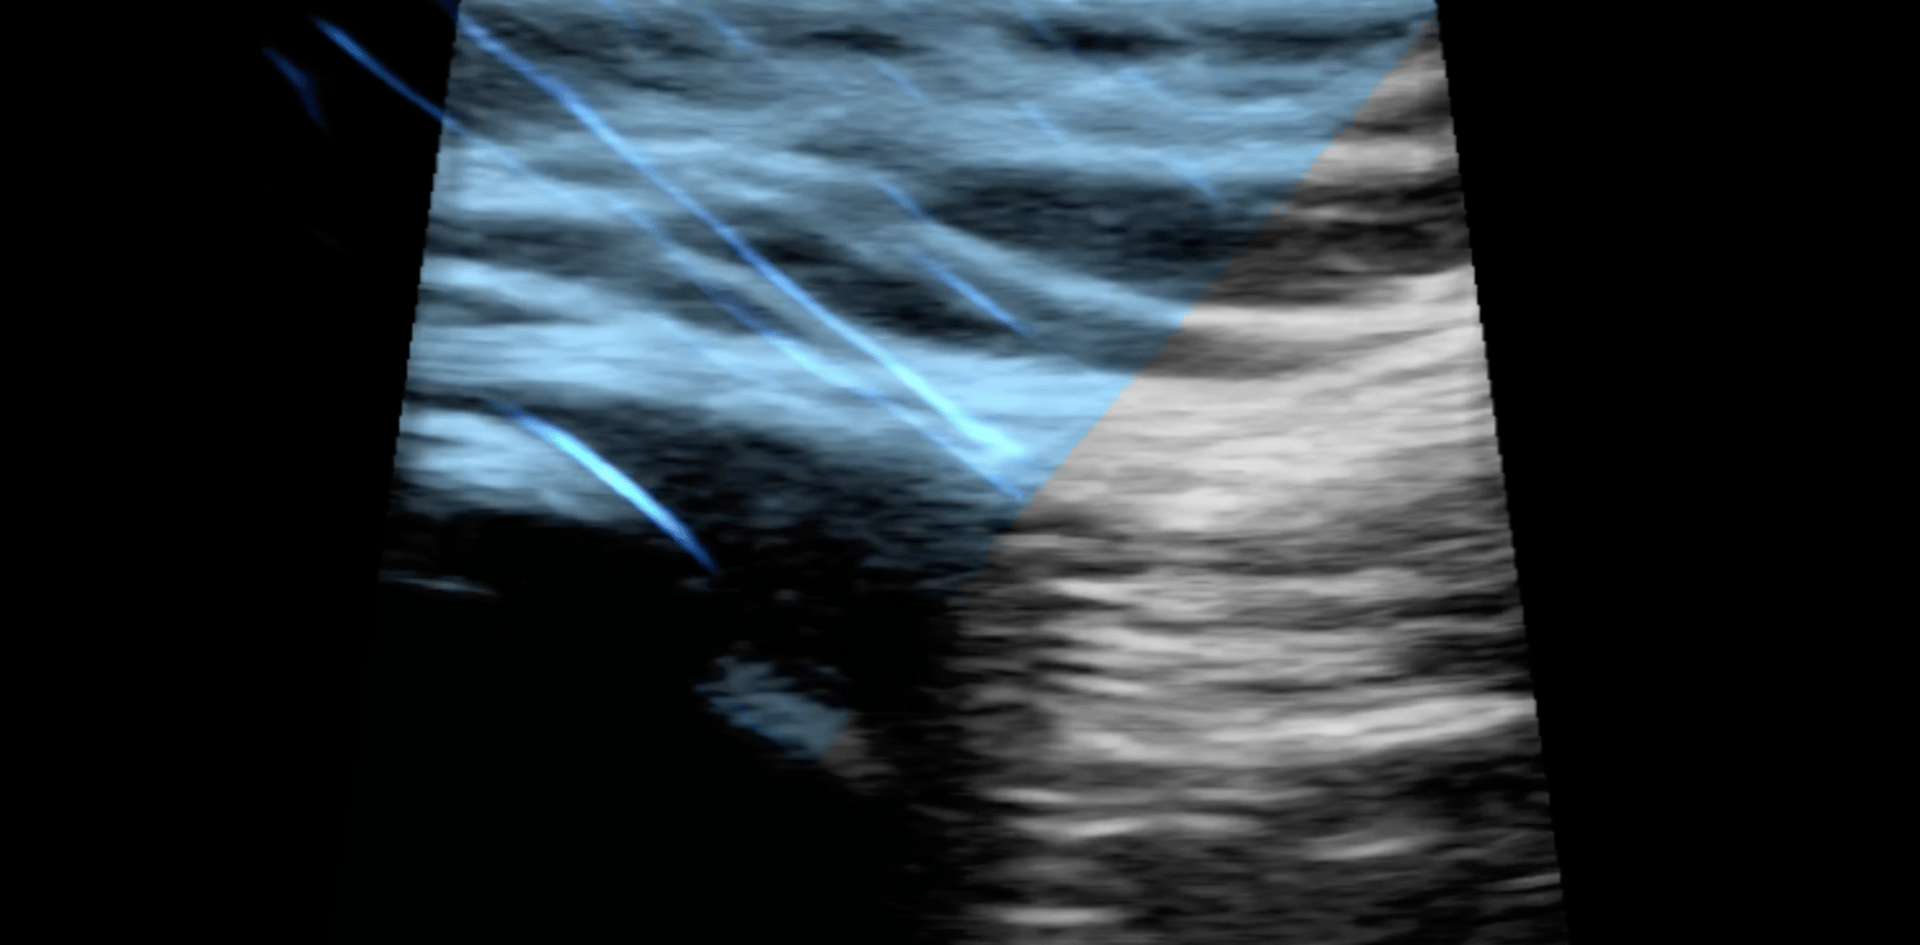

I’ve also been using ultrasound imaging in some of our courses to show the depth and angle of a needle when inserted.

Here’s an image we captured dry needling a patellar tendon. Keep an eye on the long blue streaks on the left side of the screen… those are the needles (theres only 2).